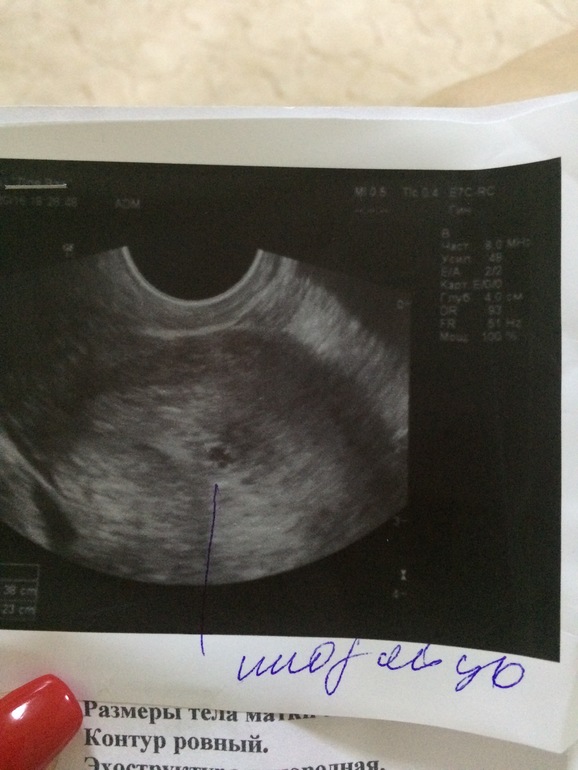

А вот мои тестики в первый же день задержки, а вечером уже были на узи и увидили плодное яйцо☺️

спасибо) на первый день задержки уже и увидили, но у меня с этим все нерегулярно, поэтому когда овулька вообще была не знаю. Вообще уже был первый скрин и по узи срок больше на неделю чем по мес)